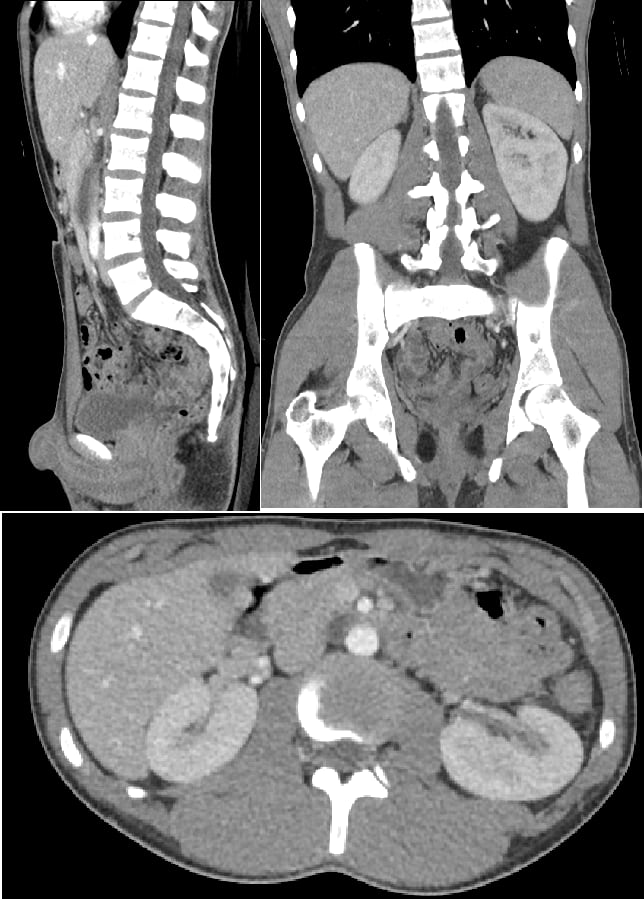

Source: bhstechltx.pages.dev Beurteilung des Gastrointestinalpatienten Gastrointestinale Erkrankungen MSD Manual Profi , Was ist eine CT-Abdomen? Eine Abdomen-CT (Computertomographie des Bauches und Beckens) ist die mittels Röntgenstrahlen erfolgende Untersuchung des Bauchraumes Hier gibt es gewaltige Dichteunterschiede der verschiedenen Gewebe zu berücksichtigen

Source: aliryanzgc.pages.dev How to interpret abdomen CT scans 3 Essential Methods , Das Ergebnis darf bei den Bilder des Abdomen CT natürlich deshalb nicht verfälscht werden. Ein Abdomen-CT wird zur Diagnose und Überwachung einer Vielzahl von Zuständen eingesetzt

Source: itseasiwke.pages.dev MRTKontrastmittel Nutzen und Nebenwirkungen , Die Abdomen-CT dient bei einer Vielzahl medizinischer Fragestellungen als wichtiges Instrument der Diagnostik.Sie erfolgt in einer großen Röhre, in der schichtweise Aufnahmen des Bereichs angefertigt und anschließend im Computer zu. Die Bildgebung der Verdauungsorgane und der Harnwege ist oftmals detaillierter, wenn man eine Kontrastierung vornimmt.